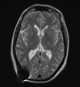

Colloid cyst of third ventricle

A colloid cyst is a non-cancerous tumor in the brain. It consists of a gelatinous material contained within a membrane of epithelial tissue. [Source: Wikipedia ]